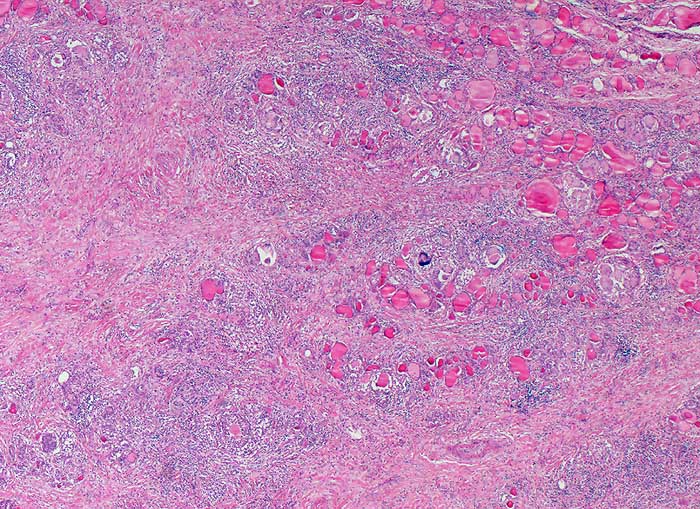

PathoPic ID 6492 - Granulomatöse Thyreoiditis de Quervain

Granulomatöse Thyreoiditis de Quervain

Entzündung / Reparatur

Schilddrüse

Endokrinium

Das Schilddrüsenparenchym wird fokal von einer granulomatösen Entzündung zerstört und ist herdförmig bereits ausgedehnt vernarbt.

Unklarer Schilddrüsentumor rechts, im Ultraschall solitär, derb, echoarmer Randraum, unscharf begrenzt, Dm 1cm.

Histologie

25